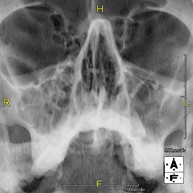

- Paranasal Sinuses X-ray

This technique uses X-ray rendered imaging for examining the paranasal sinuses. Indicated for: difficulty breathing through the nose, chronic cough, headache, mucus.